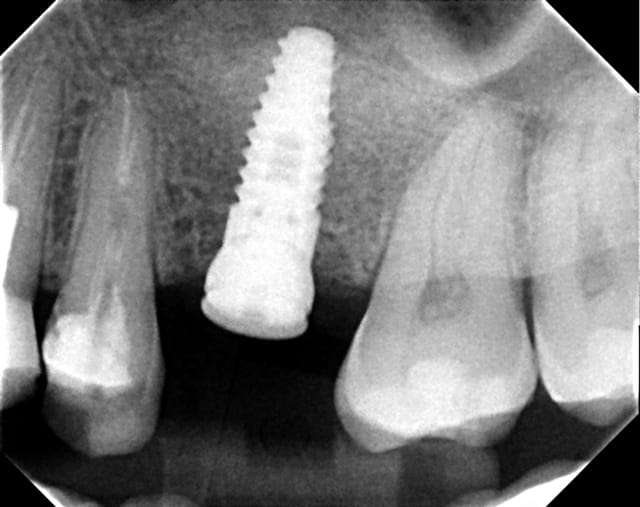

Straumann, bien qu'il soit monopièce, sans connection au niveau osseux...il perd souvent de l'os jusqu'a la première spire. 2 radio a 3 ans d'intervalle.

Straumann decembre 2011 kv7f9v - Eugenol

Straumann d cembre 2008 liqui0 - Eugenol

> Straumann, bien qu'il soit monopièce, sans connection au niveau osseux...il perd

> souvent de l'os jusqu'a la première spire. 2 radio a 3 ans d'intervalle.

Surchage ?

Placer dans une greffe osseuse ?

>Straumann, bien qu'il soit monopièce, sans connection au niveau osseux...il perd souvent >de l'os jusqu'a la première spire. 2 radio a 3 ans d'intervalle.

Oui là il y a un bug, mais je ne crois pas que le tissue level soit en cause. Pourquoi l'os est-il surchargé ?